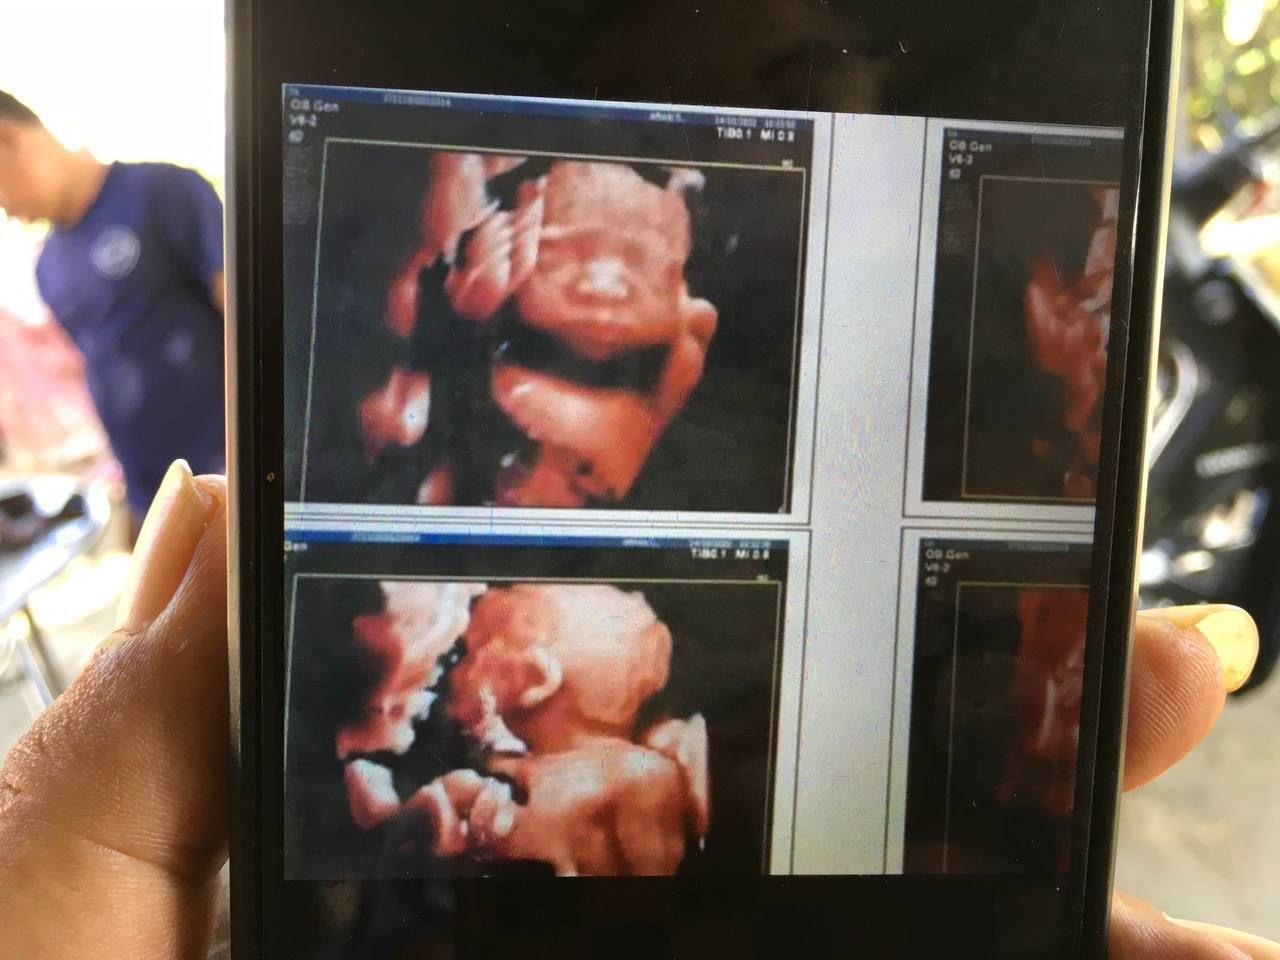

សមត្ថកិច្ចបានបន្ថែមទៀតថា លទ្ធផលក្រោយការសិក្សាតាមវិទ្យាសាស្រ្តគ្រូពេទ្យ គឺស្រ្តីម្នាក់នេះមិនមានផ្ទៃពោះទេ។ ពោលការពិនិត្យអេកូនៅមន្ទីរពេទ្យបង្អែកស្វាយទាប នៅថ្ងៃទី១៣ ខែមិថុនា ឆ្នាំ២០២២ របស់លោកវេជ្ជបណ្ឌិត សរ សុខចំរើន គឺមិនមានផ្ទៃពោះទេ, ការពិនិត្យ អេកូនៅថ្ងៃទី២៦ ខែតុលា ឆ្នាំ២០២២របស់លោក វេជ្ជបណ្ឌិត ចាន់ ថន គឺមិនមានផ្ទៃពោះទេ មិនត្រឹមតែប៉ុណ្ណោះ ឈ្មោះ សេង រតនា បានសុំឲ្យលោកវេជ្ជ ចាន់ ថន ជួយបញ្ជាក់ថា មានផ្ទៃពោះថែមទៀតផង តែលោកវេជ្ជបណ្ឌិតមិនធ្វើតាមសំណូមពរនេះ ហើយលទ្ធផលនៅថ្ងៃទី០៨ ខែវិច្ឆិកា ឆ្នាំ២០២២ ការពិនិត្យរបស់គ្រូពេទ្យនៅមន្ទីរពេទ្យខេត្តស្វាយរៀង ក៏បញ្ជាក់ថាគ្មានផ្ទៃពោះដែរ។